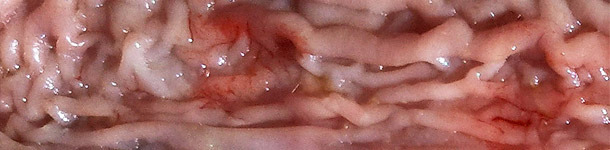

Respuestas sobre pleuroneumonía por App (2/2): diagnóstico, monitorización y erradicación

En este segundo articulo Antonio Vela, Francisco José Pallarés y David Espigares nos responden a preguntas sobre diagnóstico, monitorización y erradicación de la pleuroneumonía causada por Actinobacillus pleuropneumoniae (App).